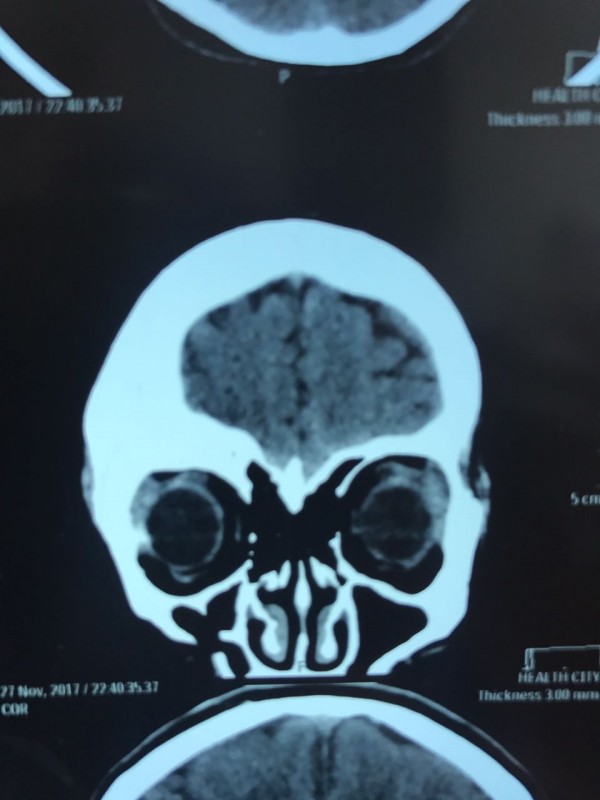

Как рассказал врач-нейрохирург городской клинической больницы № 7 Алматы Константин Ли, предварительный диагноз пациента - "фиброзная дисплазия лобной кости справа", то есть опухолевое поражение костей черепа. По его словам, сложность и уникальность операции в том, что опухоль плотно соприкасалась со зрительным нервом.

"Компьютерная томография показала, что костная опухоль поражала лобную кость и "крышу" орбиты глаза, которая, в свою очередь, сдавливала глазное яблоко. Чтобы убрать опухоль, потребовалось немало времени. Наша задача была сохранить глазное яблоко, зрительный нерв и сосуды. Если неправильно провести операцию и неправильно закрыть дефект, то в последующем это может привести к эстетической неполноте и асимметрии лица. Уникальность еще и в том, что в операции применялась 3D-стереолитография, которая делается только в Алматы", - рассказал он.

Снимок черепа. Опухоль с левой стороны. Фото предоставлено Константином Ли

Снимок сделан до операции. Фото предоставлено Константином Ли